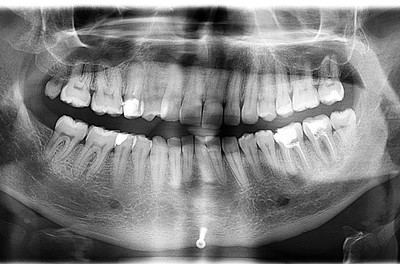

Вам сказали фигню! Вот снимок этой пациентки до лечения.

Как стоматолог, поясняю - здесь проводится ортодонтическое лечение. Явно не просто так, у пациентки были проблемы прикуса, которые привели к снижению межальвеолярной высоты. Это означает, что нижняя челюсть вывернута вверх и кпереди от своего нормального положения, что приводит к перенепряжению групп мышц вплоть до нарушения кровоснабжения головы и шеи. Кто не видит логики - постоянный гипертонус мышц пережимает сосуды. Попробуйте выдвинуть нижнюю челюсть вперед и кверху - через несколько минут заболит голова. При снижении высоты прикуса это становится хроническим, организм начинает рефлекторно сбрасывать это напряжение задействуя другие группы мышц.